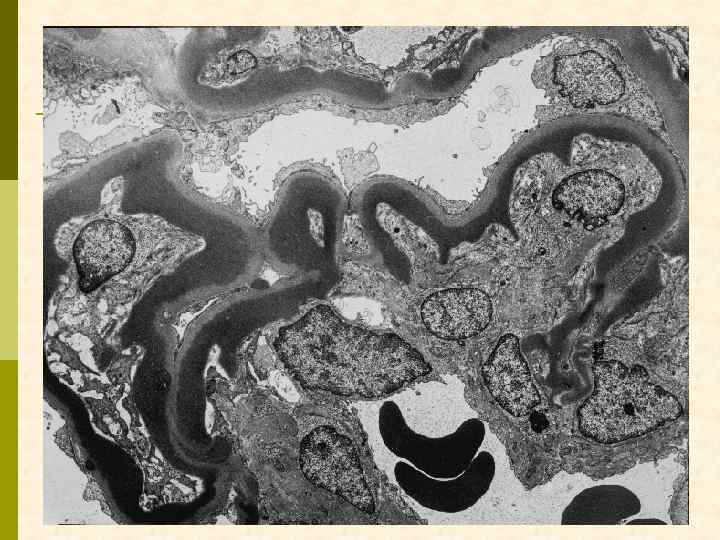

* * C Ядро эндотелиоцита C

Эритроцит МПГН, III тип. Грубые изменения ГБМ, резкое утолщение, лакуны, истончение плотной пластины, субэпителиальные депозиты